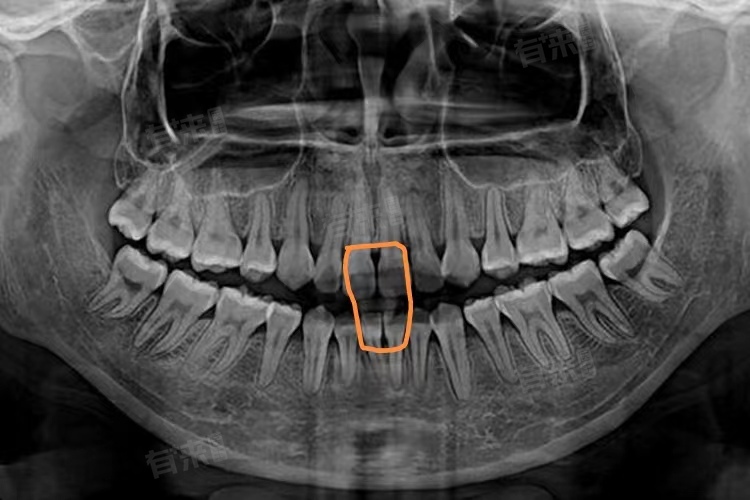

- 小视野扫描价格通常在150-300元,小视野扫描范围<10cm×10cm,主要应用于局限性病变的诊断,如颞下颌关节紊乱病、根尖周病变、牙体牙髓病、牙周炎、根折、多生牙及阻生牙的定位等。由于其扫描范围有限,辐射剂量较低,设备使用成本也相对少,所以价格较为便宜。

- 当患者病情复杂,如存在多颗牙齿的问题、需要进行复杂的口腔手术等,可能会使用更先进和精确的设备,如锥形束CT(CBCT),检查费用也会相应提高,可能达到400-800元。

- CBCT采用新型口腔三维数字成像技术,空间分辨率高,对于牙齿根管系统、下颌骨、下颌神经管、颞下颌关节细微硬组织结构的成像质量更好,能提供更详细、三维的牙齿和颌骨图像,有助于医生更准确地评估病情、制定手术方案以及预测治疗效果,所以价格更高。